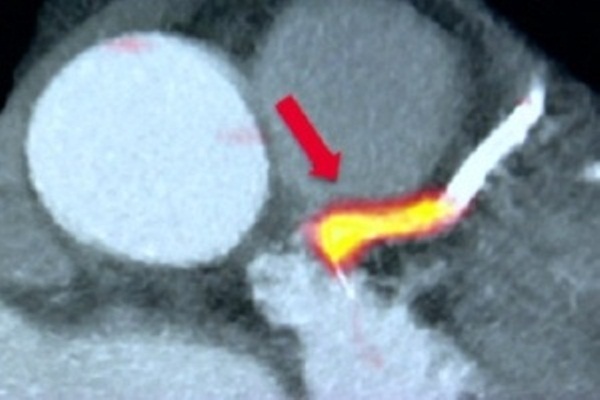

Eles usaram um marcador radiativo – uma substância química que ajuda a detectar as placas. Os cientistas conseguem visualizar essas placas com imagens de alta resolução do coração e das veias sanguíneas.

Assim, eles conseguem obter um retrato detalhado do coração, com as zonas de perigo claramente identificadas. Uma técnica semelhante é usada para detectar o local exato de tumores em pacientes com câncer.